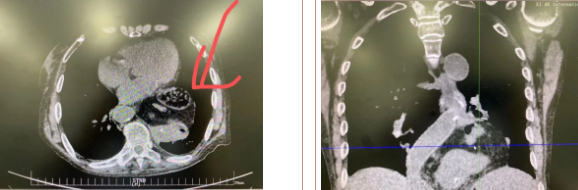

據(jù)了解,患者多年來進(jìn)食后出現(xiàn)惡心、嘔吐,卻未到醫(yī)院進(jìn)行檢查。3個月前患者突然出現(xiàn)無尿,全身腫脹等情況才前往就醫(yī),卻遭多家醫(yī)院拒收,輾轉(zhuǎn)來到我院就診。檢查發(fā)現(xiàn)患者已患宮頸癌、進(jìn)而引起腎后性腎衰、同時合并膈疝、出現(xiàn)泌尿道感染,病情及其復(fù)雜。

經(jīng)泌尿外科積極救治,患者腎衰癥狀緩解,隨后轉(zhuǎn)入放射治療中心進(jìn)行宮頸癌根治性放療。放療期間,患者惡心、嘔吐癥狀逐漸加重,后期無法進(jìn)食,排除機(jī)械性腸梗阻和放療因素,考慮因長期膈疝加重引起,經(jīng)胸外科會診后轉(zhuǎn)入胸外科一病區(qū)準(zhǔn)備手術(shù)治療。

麻醉手術(shù)中心副主任丁倩為減輕患者術(shù)后不適,實(shí)施單腔聯(lián)合支氣管封堵插管,同時進(jìn)行了肋間神經(jīng)阻滯麻醉。術(shù)中發(fā)現(xiàn)患者膈疝巨大,食管和疝囊分界不清,部分胃組織和結(jié)腸疝已進(jìn)入胸腔。李文海憑借豐富的臨床經(jīng)驗(yàn),仔細(xì)辨別解剖變異,有序完成分離、縫合、修補(bǔ)等一系列操作,胸外科穆強(qiáng)副主任醫(yī)師、劉歡住院醫(yī)師、麻醉手術(shù)中心團(tuán)隊(duì)通力配合,手術(shù)最終順利完成,患者安全返回胸外科監(jiān)護(hù)室病房。目前患者術(shù)后恢復(fù)良好,于近日準(zhǔn)備出院。